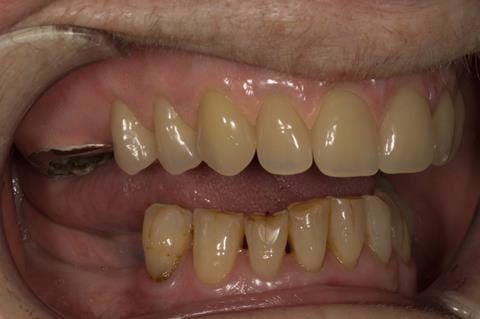

- Eight mandibular anterior teeth worn incisal edges from now extracted maxillary anterior crowns. Gingivitis - owing to inadequate oral hygiene.

- LL6 with large amalgam restoration - healthy periodontium.

- Cobalt chromium reinforced gasket denture - using a Molloplast B "O" ring to retain and stabilise the denture. This was my professional preference as this was the least invasive and simplest solution to this dental problem. Should the UR7 require removal in the future - an artificial tooth could be added - resulting in a complete denture. The patient would have adapted to the denture fully by this stage and have good neuromuscular control of the prosthesis.

Following consultation and second discussion appointment the patient chose to have option 2 namely, a window denture - maxillary cobalt chromium based partial denture. The clinical situation and treatment process is shown in detail below with photographs. The patient was successfully rehabilitated with this and her quality of life considerably improved. The clinical work was provided by Finlay and the technical work by Rowan.